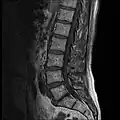

MRI

-

MRI lumbar spine with degeneration (sagittal T2 FRFSE) -

MRI lumbar spine with degeneration (sagittal T1 FSE) -

MRI lumbar spine with degeneration (sagittal FAST STIR) -